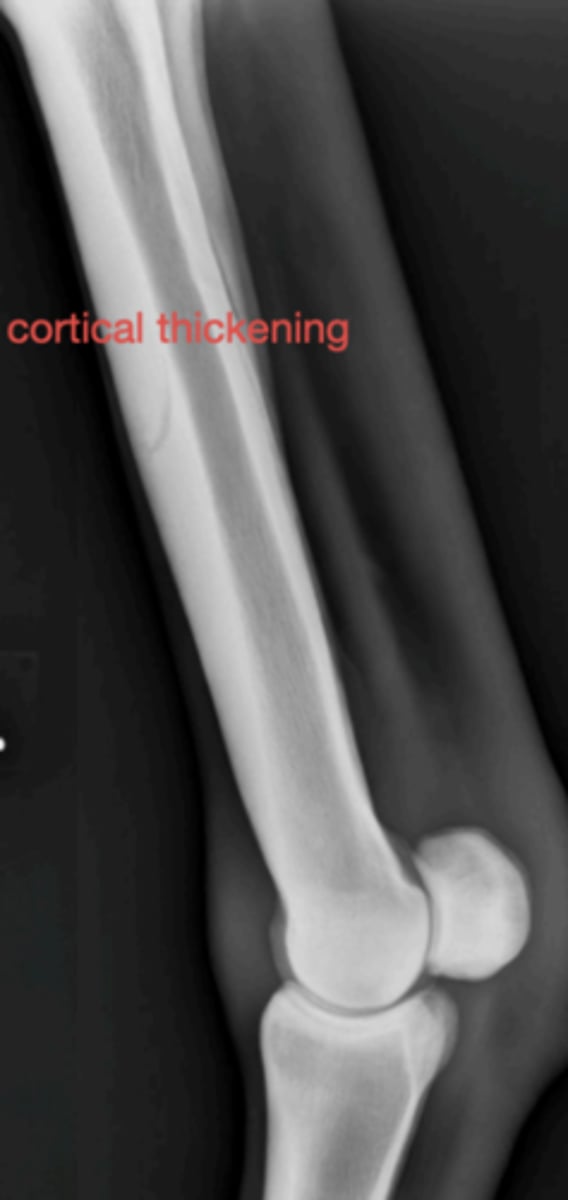

Metacarpal periositis

3 y/o horse with metacarpal pain; radiograph shows bone thickening- what caused this?

10 y/o German Shepherd comes in with lameness on the right hind leg; what is the radiographic finding?

Hypertrophic osteodystrophy